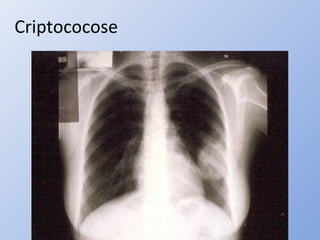

• Pulmonar

– Rx: nódulos isolados ou múltiplos nos campos pulmonares

médio e inferior

Criptococose